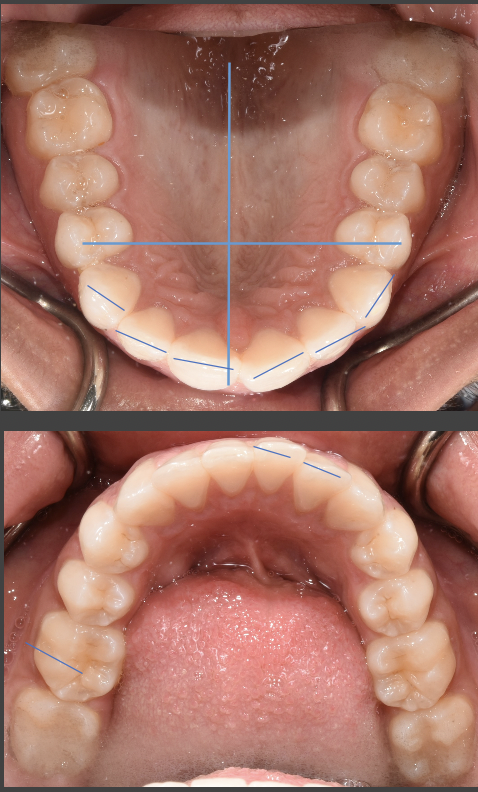

My daughter has some spacing in her teeth. Some misshaped teeth and her top and bottom row doesn’t match up and I wanted to know from the looks does it look like she needs braces? She also bites down on her jaw alot

Its hard to diagnose from the picture alone, with her mouth open and not in centric (closed and relaxed) occlusion. It appears from the picture that she has most or all of her permanent dentition. This is the perfect time to schedule a complimentary consultation with a preferred orthodontist in your area. Its not clear what you mean by "biting down on her jaw a lot", however I am assuming it means her bite is different than yours and its possible that it feels uncomfortable to her. Spacing and small or misshaped teeth are cosmetic, however if she is in malocclusion, these can all be addressed with orthodontics. Most orthodontists will evaluate your daughter at little to no cost to you. It is always a good idea to get more than one opinion prior to making a decision with treatment.